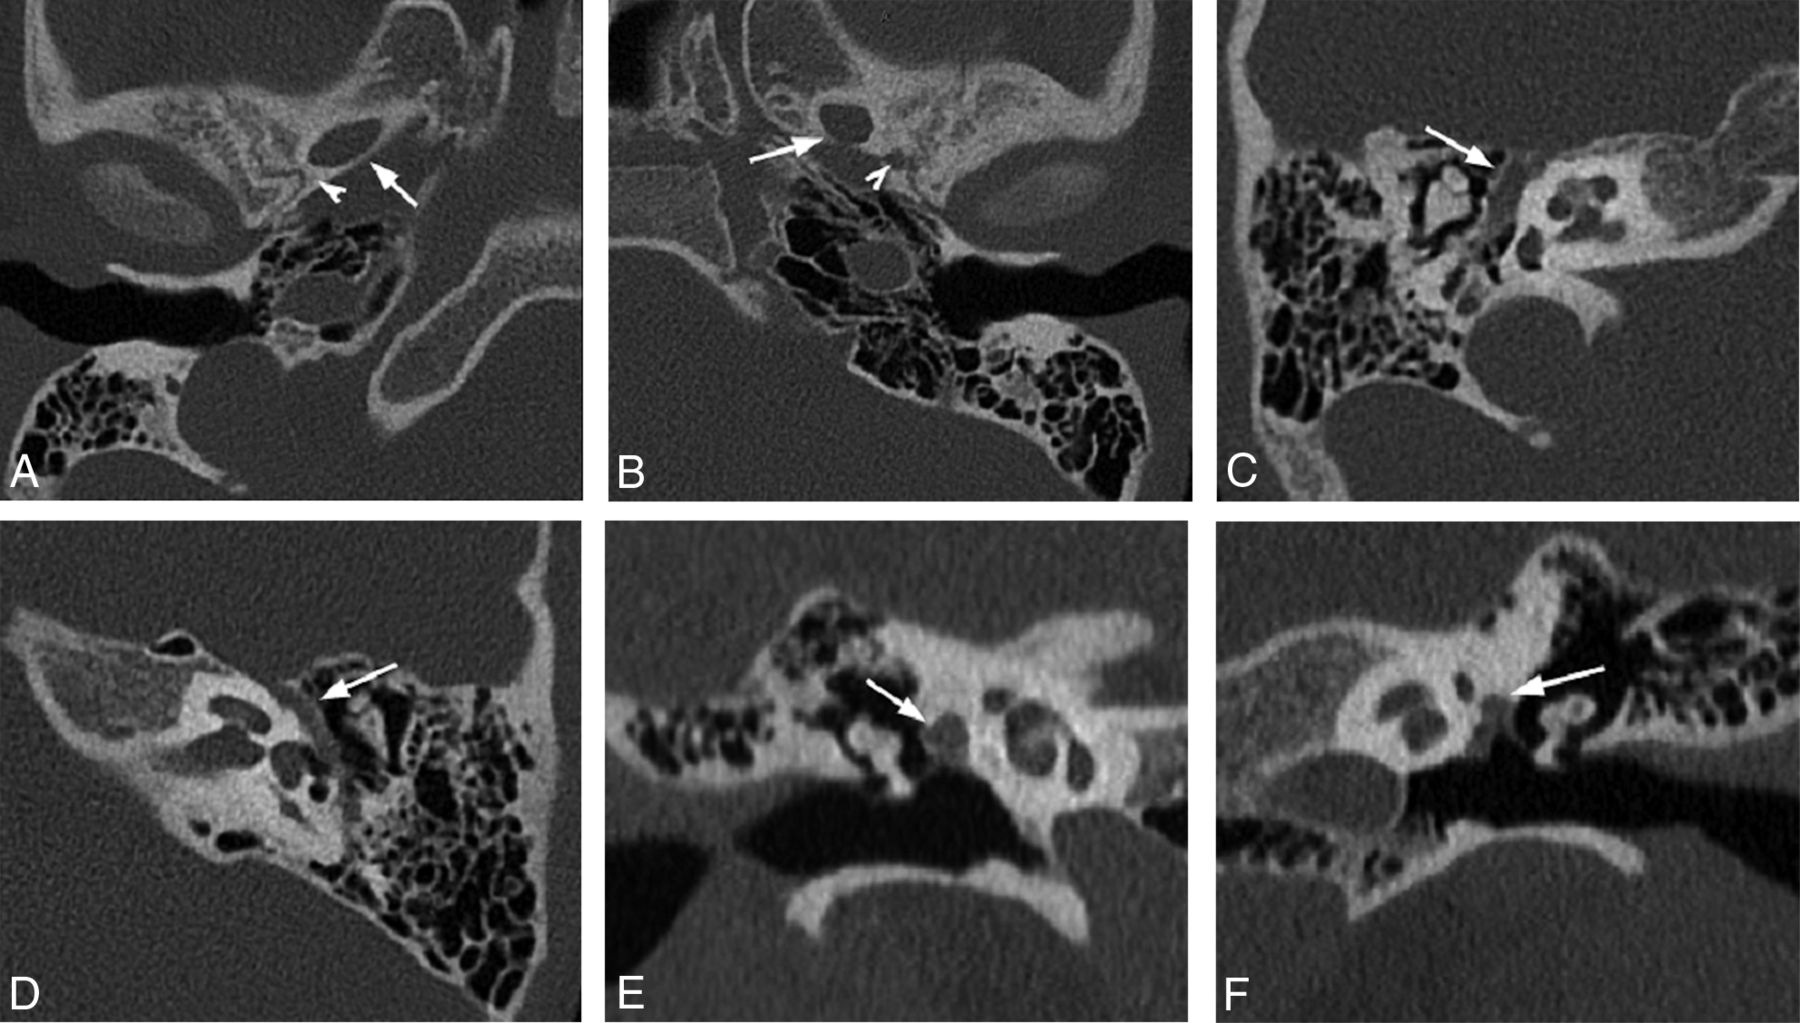

Imaging Signs: “Three-Eyed Snail” Sign

As previously discussed, an osseous canal sometimes separates the facial nerve and the stapedial artery. This results in a characteristic appearance on coronal imaging planes, predictably altering the common anatomic radiologic landmark known as the “snail eyes.” The usual “2 eyes” correspond to the labyrinthine and tympanic segments of the facial nerve in cross-section; the snail shell is implied by the cochlear spiral. In cases of PSA with a duplicated facial nerve canal, a rounded soft tissue mass lateral to the tympanic segment of the facial nerve is seen in the coronal plane, giving the impression of a “third eye” (Fig 5A, -B). This sign was observed in 6 of 10 PSA cases (60%) in our series.

Right ear (A) and left ear (B) coronal CT images from 2 patients demonstrate an additional lumen lateral to the tympanic facial canal (“3-eyed snail”) representing the bifurcation of the PSA as it traverses the floor of the middle cranial fossa to give rise the middle meningeal artery (white arrows). Labyrinthine (black arrows) and tympanic (white arrowheads) segments of the facial nerve represent usually seen “2 eyes of the snail.” Right ear (C) and left ear (D) axial CT images in the same patients demonstrate duplication of the anterior segment of the tympanic facial nerve canal (white arrows). The labyrinthine segment (black arrows), tympanic segment (white arrowheads), and PSA canal intersect to form an “N” on the left (D) and a reverse “N” on the right (C). Geniculate ganglion is seen anteromedially (black arrowheads). TT = tensor tympani.

Imaging Signs: “N” Sign

As an axial corollary to the “3-eyed snail” sign, PSA can have a characteristic appearance at the level of the geniculate ganglion. Here, the distal tympanic segment of the PSA appears as a tubular soft tissue attenuation coursing lateral to tympanic segment of the facial canal. This attenuation adds an additional limb to the classic upside down “V” shape of the facial nerve canal at the level of the geniculate ganglion, transforming the “V” into an “N” if on the left and reverse “N” if on the right side (Fig 5C, -D). Expectedly, this sign was also observed in 6 of 10 PSA cases (60%) in our series.